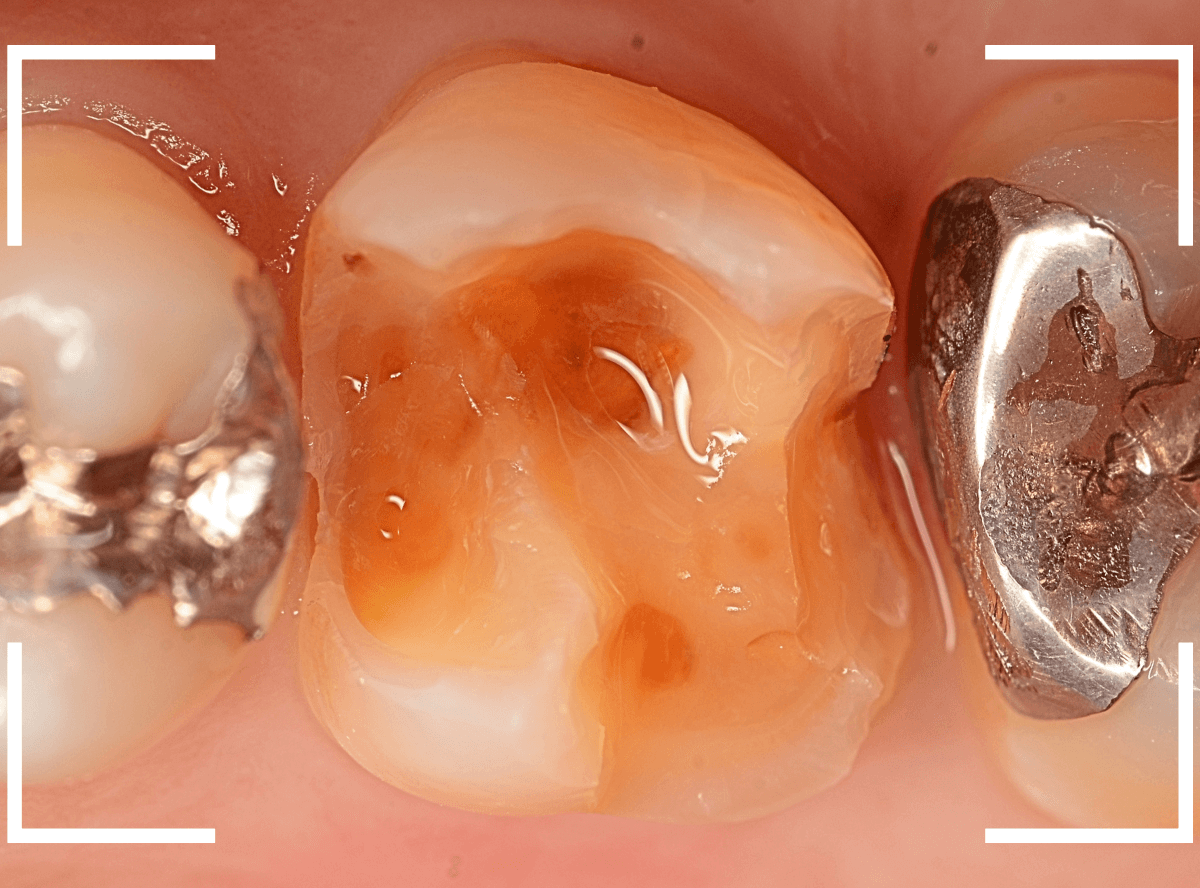

Case.9 金属の下で深い虫歯

レントゲン写真で金属のつめものの中の虫歯が見つかった方です。

つめものの中の虫歯の厄介なところは、自覚症状がない事も多い事です。

さて、外から見た感じでは、私が見ても中で虫歯進行してるかわかりません。

症状がなくても、定期メンテナンスとレントゲン写真を使った確認が有用です。

虫歯の治療を開始してつめものを外したところです。

左側の歯は、つめものの下のお薬の中で落とし穴のように虫歯になっていました。

右側の歯の赤く染まっている部分も虫歯です。

左側の歯のお薬を全部除去しました。

全ての虫歯を除去しました。

かなり中で広がっていた虫歯でした。

虫歯は見た目や症状からだけで判断できません。